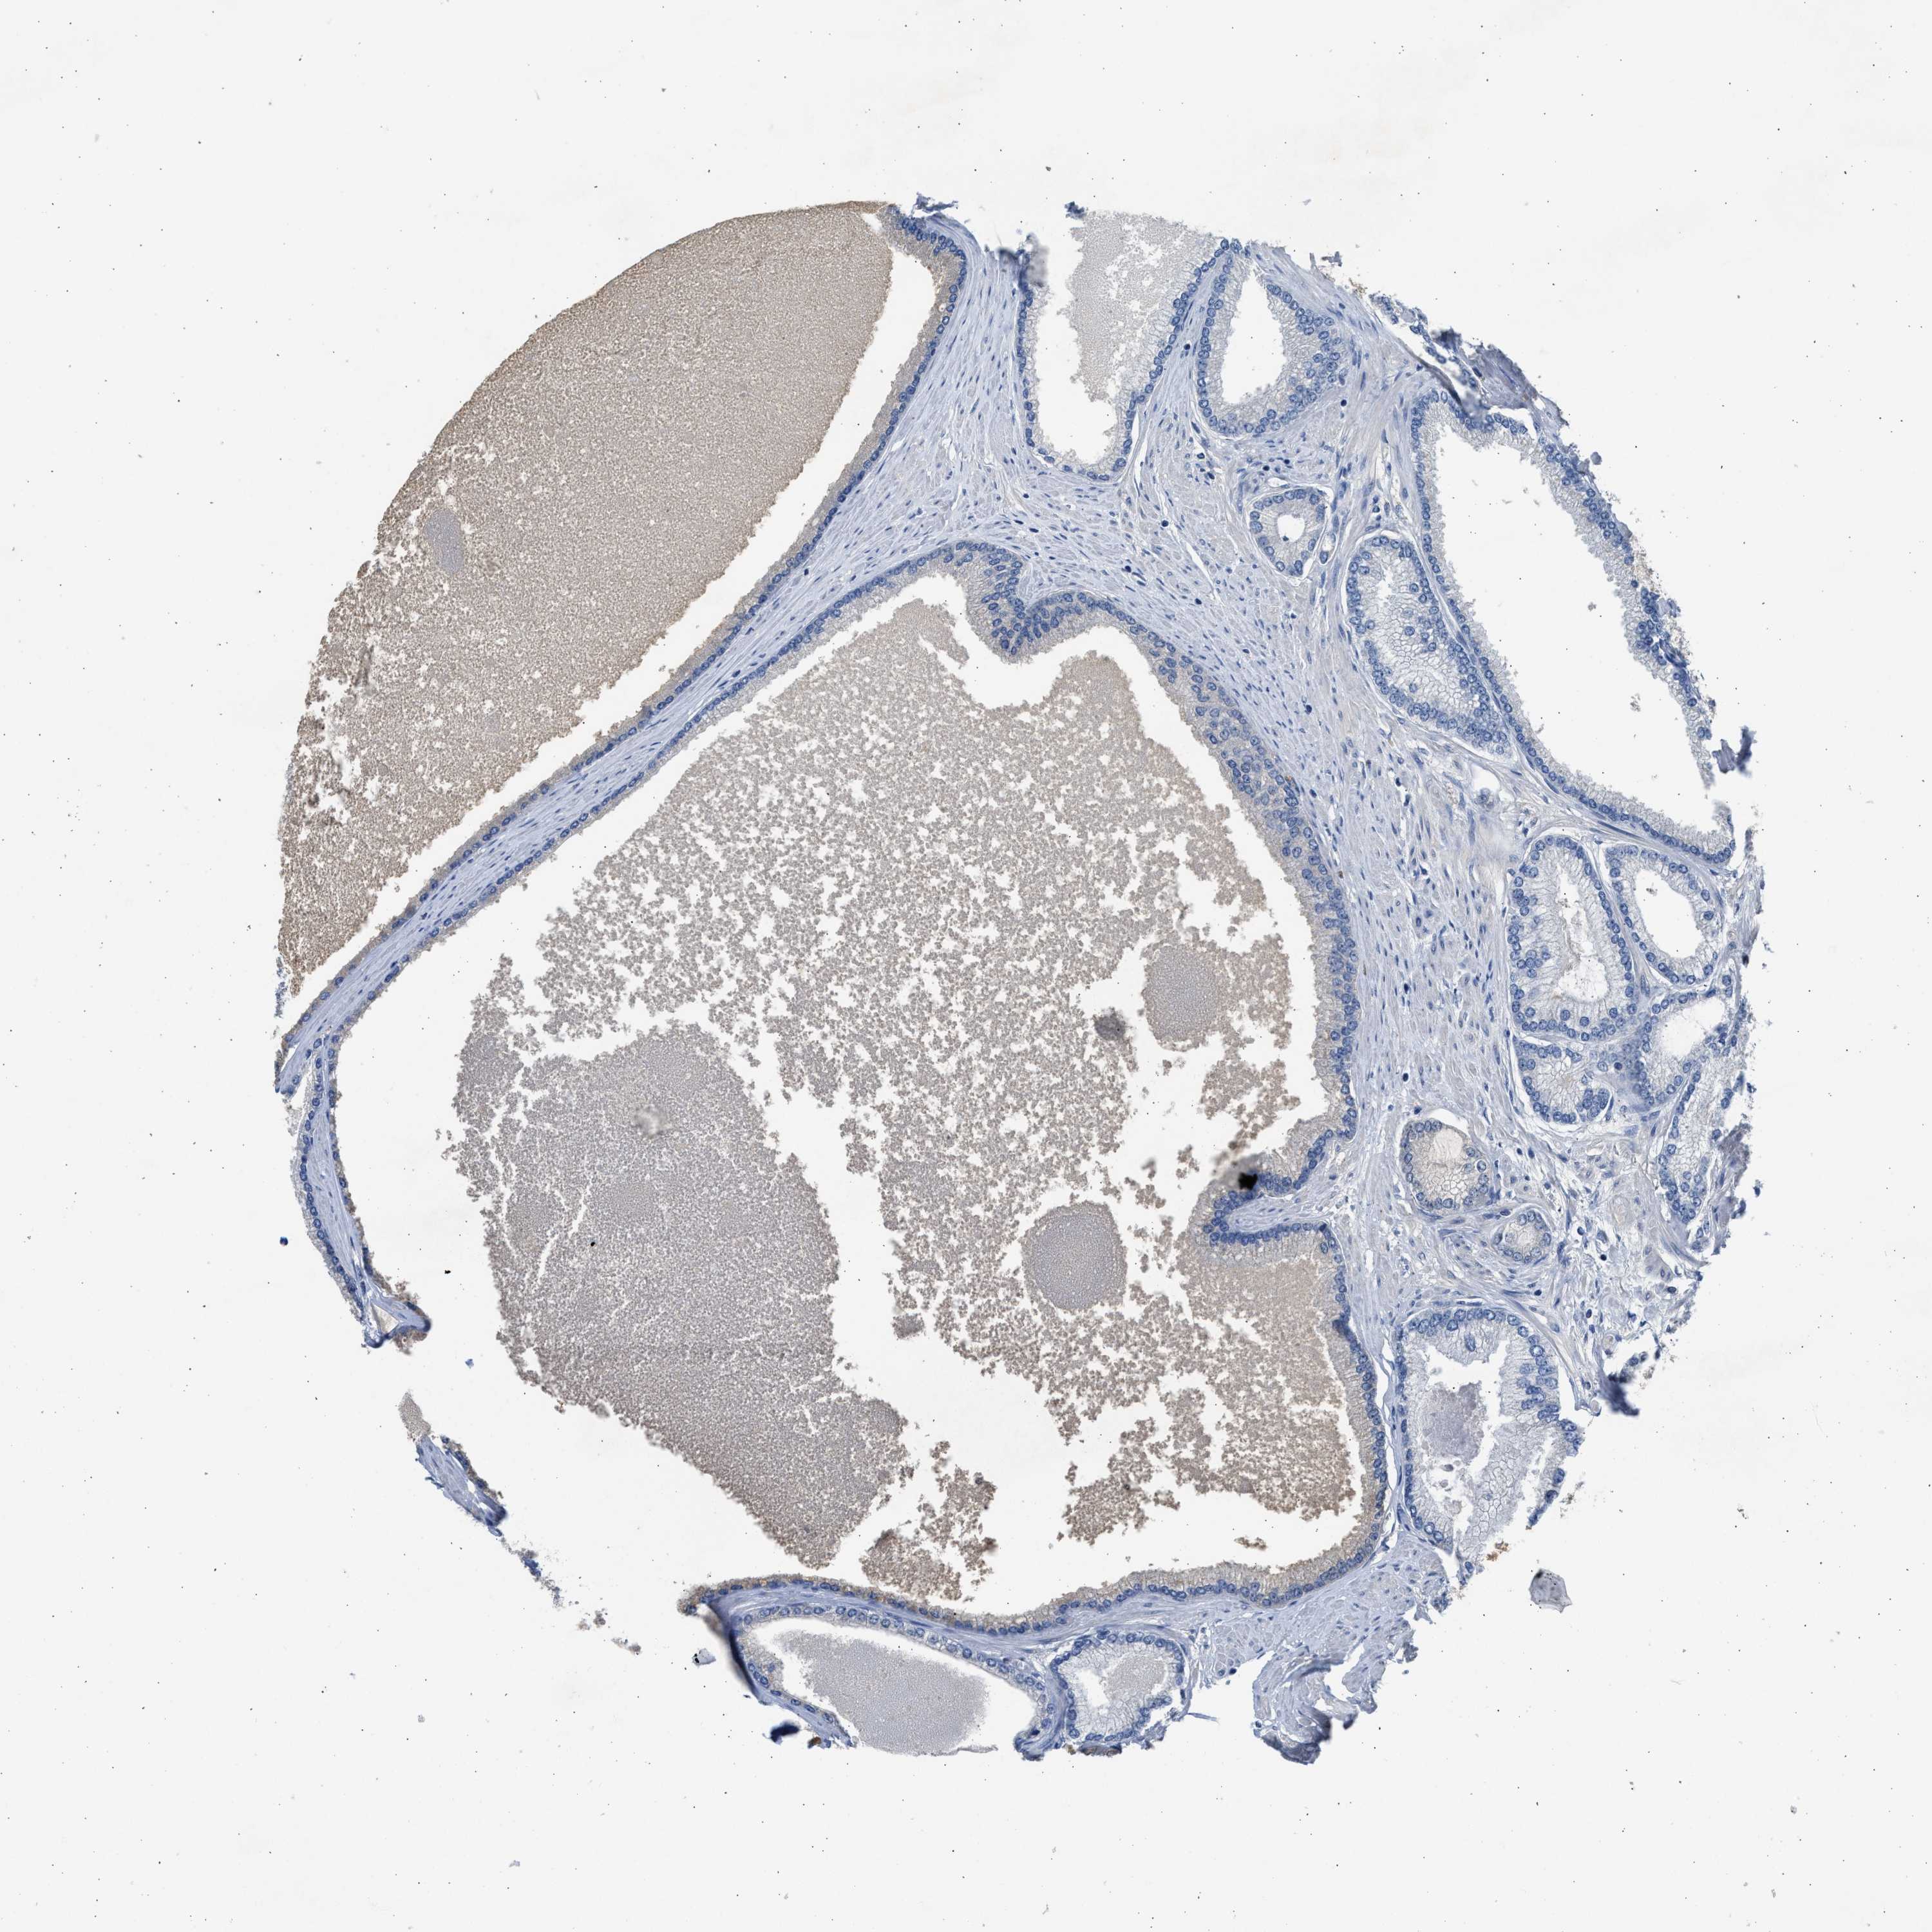

PROSTATE CANCER - Protein expressioni

A mouse-over function shows sample information and annotation data. Click on an image to view it in a full screen mode. Samples can be filtered based on level of antibody staining by selecting one or several of the following categories: high, medium, low and not detected. The assay and annotation is described here.

Antibody stainingi

Antibody staining in the annotated cell types in the current human tissue is reported as not detected, low, medium, or high, based on conventional immunohistochemistry profiling in selected tissues. This score is based on the combination of the staining intensity and fraction of stained cells.

Each image is clickable and will lead to virtual microscopy that enables deeper exploration of all samples and also displays staining intensity scores, fraction scores and subcellular localization as well as patient and tissue information for each sample.

Antibody HPA041487

Antibody HPA063633

Antibody CAB018755

Staining

High

Medium

Low

Not detected

Intensity

Strong

Moderate

Weak

Negative

Quantity

>75%

75%-25%

<25%

None

Location

Nuclear

Cytoplasmic/membranous

Cytoplasmic/membranous,nuclear

Adenocarcinoma, NOS

Adenocarcinoma, High grade

Adenocarcinoma, Low grade